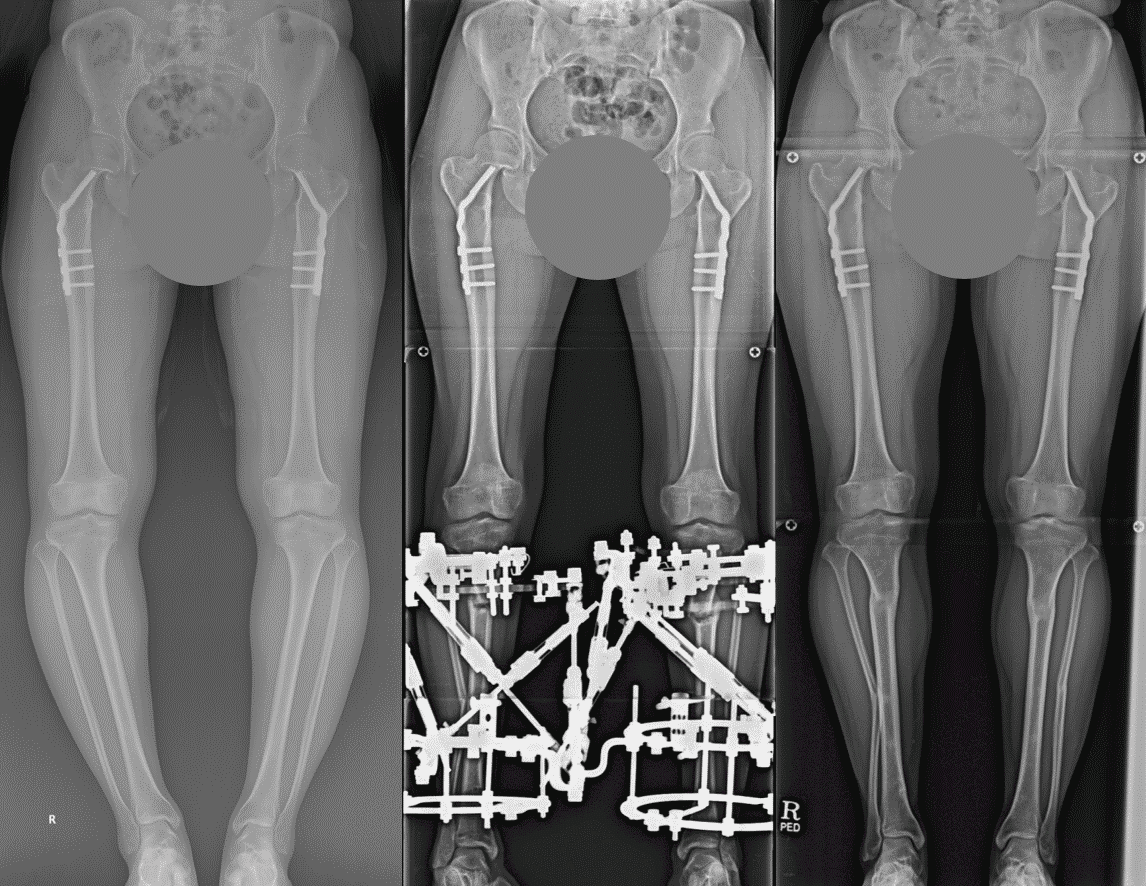

Limb Lengthening Surgery Before and After Photos Limb Lengthening

Limb Lengthening Surgery Before and After Photos Limb Lengthening How Much Is Limb Lengthening Surgery In Korea The cheapest countries for limb lengthening surgery in the world include india, turkey, mexico, thailand, and colombia, where you can find excellent care. Explore the top limb lengthening surgeons, methods and costs worldwide in our guide. For the maximum height gain possible (6 inches), the cost is more than. Limb lengthening surgery, depending on the patient and the specific surgery,. How Much Is Limb Lengthening Surgery In Korea.

Limb Lengthening Surgery Before and After Photos Limb Lengthening How Much Is Limb Lengthening Surgery In Korea $48,500 for both upper and lower legs. The price for the limb lengthening surgery with assoc. Discover the best options for height increase. For the maximum height gain possible (6 inches), the cost is more than. The cheapest countries for limb lengthening surgery in the world include india, turkey, mexico, thailand, and colombia, where you can find excellent care. Find. How Much Is Limb Lengthening Surgery In Korea.

Limb Lengthening Surgery Before and After Photos Limb Lengthening How Much Is Limb Lengthening Surgery In Korea For the maximum height gain possible (6 inches), the cost is more than. How much is leg lengthening surgery to gain the max height? The cheapest countries for limb lengthening surgery in the world include india, turkey, mexico, thailand, and colombia, where you can find excellent care. Explore the top limb lengthening surgeons, methods and costs worldwide in our guide.. How Much Is Limb Lengthening Surgery In Korea.

Limb Lengthening Surgery Before and After Photos Limb Lengthening How Much Is Limb Lengthening Surgery In Korea The cheapest countries for limb lengthening surgery in the world include india, turkey, mexico, thailand, and colombia, where you can find excellent care. Limb lengthening surgery, depending on the patient and the specific surgery, can cost from 40 million won to 80 million won. $48,500 for both upper and lower legs. Explore the top limb lengthening surgeons, methods and costs. How Much Is Limb Lengthening Surgery In Korea.

Limb Lengthening Surgery Before and After Photos Limb Lengthening How Much Is Limb Lengthening Surgery In Korea Find limb lengthening surgery procedure, recovery time, leg lengthening surgery cost in korea, cosmetic leg lengthening surgery before and after photos. Discover the best options for height increase. $48,500 for both upper and lower legs. Find the best limb lengthening surgery clinics & hospitals in south korea compare clinics, read patients’ reviews and check cost | clinics on call. The. How Much Is Limb Lengthening Surgery In Korea.

Limb Lengthening Surgery Before and After Photos Limb Lengthening How Much Is Limb Lengthening Surgery In Korea Explore the top limb lengthening surgeons, methods and costs worldwide in our guide. The price for the limb lengthening surgery with assoc. The cheapest countries for limb lengthening surgery in the world include india, turkey, mexico, thailand, and colombia, where you can find excellent care. Discover the best options for height increase. For the maximum height gain possible (6 inches),. How Much Is Limb Lengthening Surgery In Korea.

Limb Lengthening Surgery Before and After Photos Limb Lengthening How Much Is Limb Lengthening Surgery In Korea Find limb lengthening surgery procedure, recovery time, leg lengthening surgery cost in korea, cosmetic leg lengthening surgery before and after photos. Discover the best options for height increase. The cheapest countries for limb lengthening surgery in the world include india, turkey, mexico, thailand, and colombia, where you can find excellent care. The price for the limb lengthening surgery with assoc.. How Much Is Limb Lengthening Surgery In Korea.

Limb Lengthening Surgery Before and After Photos Limb Lengthening How Much Is Limb Lengthening Surgery In Korea Find limb lengthening surgery procedure, recovery time, leg lengthening surgery cost in korea, cosmetic leg lengthening surgery before and after photos. Limb lengthening surgery, depending on the patient and the specific surgery, can cost from 40 million won to 80 million won. The price for the limb lengthening surgery with assoc. For the maximum height gain possible (6 inches), the. How Much Is Limb Lengthening Surgery In Korea.

Limb Lengthening Surgery Before and After Photos Limb Lengthening How Much Is Limb Lengthening Surgery In Korea $48,500 for both upper and lower legs. Find the best limb lengthening surgery clinics & hospitals in south korea compare clinics, read patients’ reviews and check cost | clinics on call. Explore the top limb lengthening surgeons, methods and costs worldwide in our guide. Discover the best options for height increase. Limb lengthening surgery, depending on the patient and the. How Much Is Limb Lengthening Surgery In Korea.

Limb Lengthening Surgery Before and After Photos Limb Lengthening How Much Is Limb Lengthening Surgery In Korea The price for the limb lengthening surgery with assoc. For the maximum height gain possible (6 inches), the cost is more than. $48,500 for both upper and lower legs. Limb lengthening surgery, depending on the patient and the specific surgery, can cost from 40 million won to 80 million won. Discover the best options for height increase. Find limb lengthening. How Much Is Limb Lengthening Surgery In Korea.

Limb Lengthening Surgery Before and After Photos Limb Lengthening How Much Is Limb Lengthening Surgery In Korea Explore the top limb lengthening surgeons, methods and costs worldwide in our guide. The price for the limb lengthening surgery with assoc. Find the best limb lengthening surgery clinics & hospitals in south korea compare clinics, read patients’ reviews and check cost | clinics on call. How much is leg lengthening surgery to gain the max height? The cheapest countries. How Much Is Limb Lengthening Surgery In Korea.

Limb Lengthening Surgery Before and After Photos Limb Lengthening How Much Is Limb Lengthening Surgery In Korea For the maximum height gain possible (6 inches), the cost is more than. Explore the top limb lengthening surgeons, methods and costs worldwide in our guide. Discover the best options for height increase. The price for the limb lengthening surgery with assoc. $48,500 for both upper and lower legs. Find limb lengthening surgery procedure, recovery time, leg lengthening surgery cost. How Much Is Limb Lengthening Surgery In Korea.